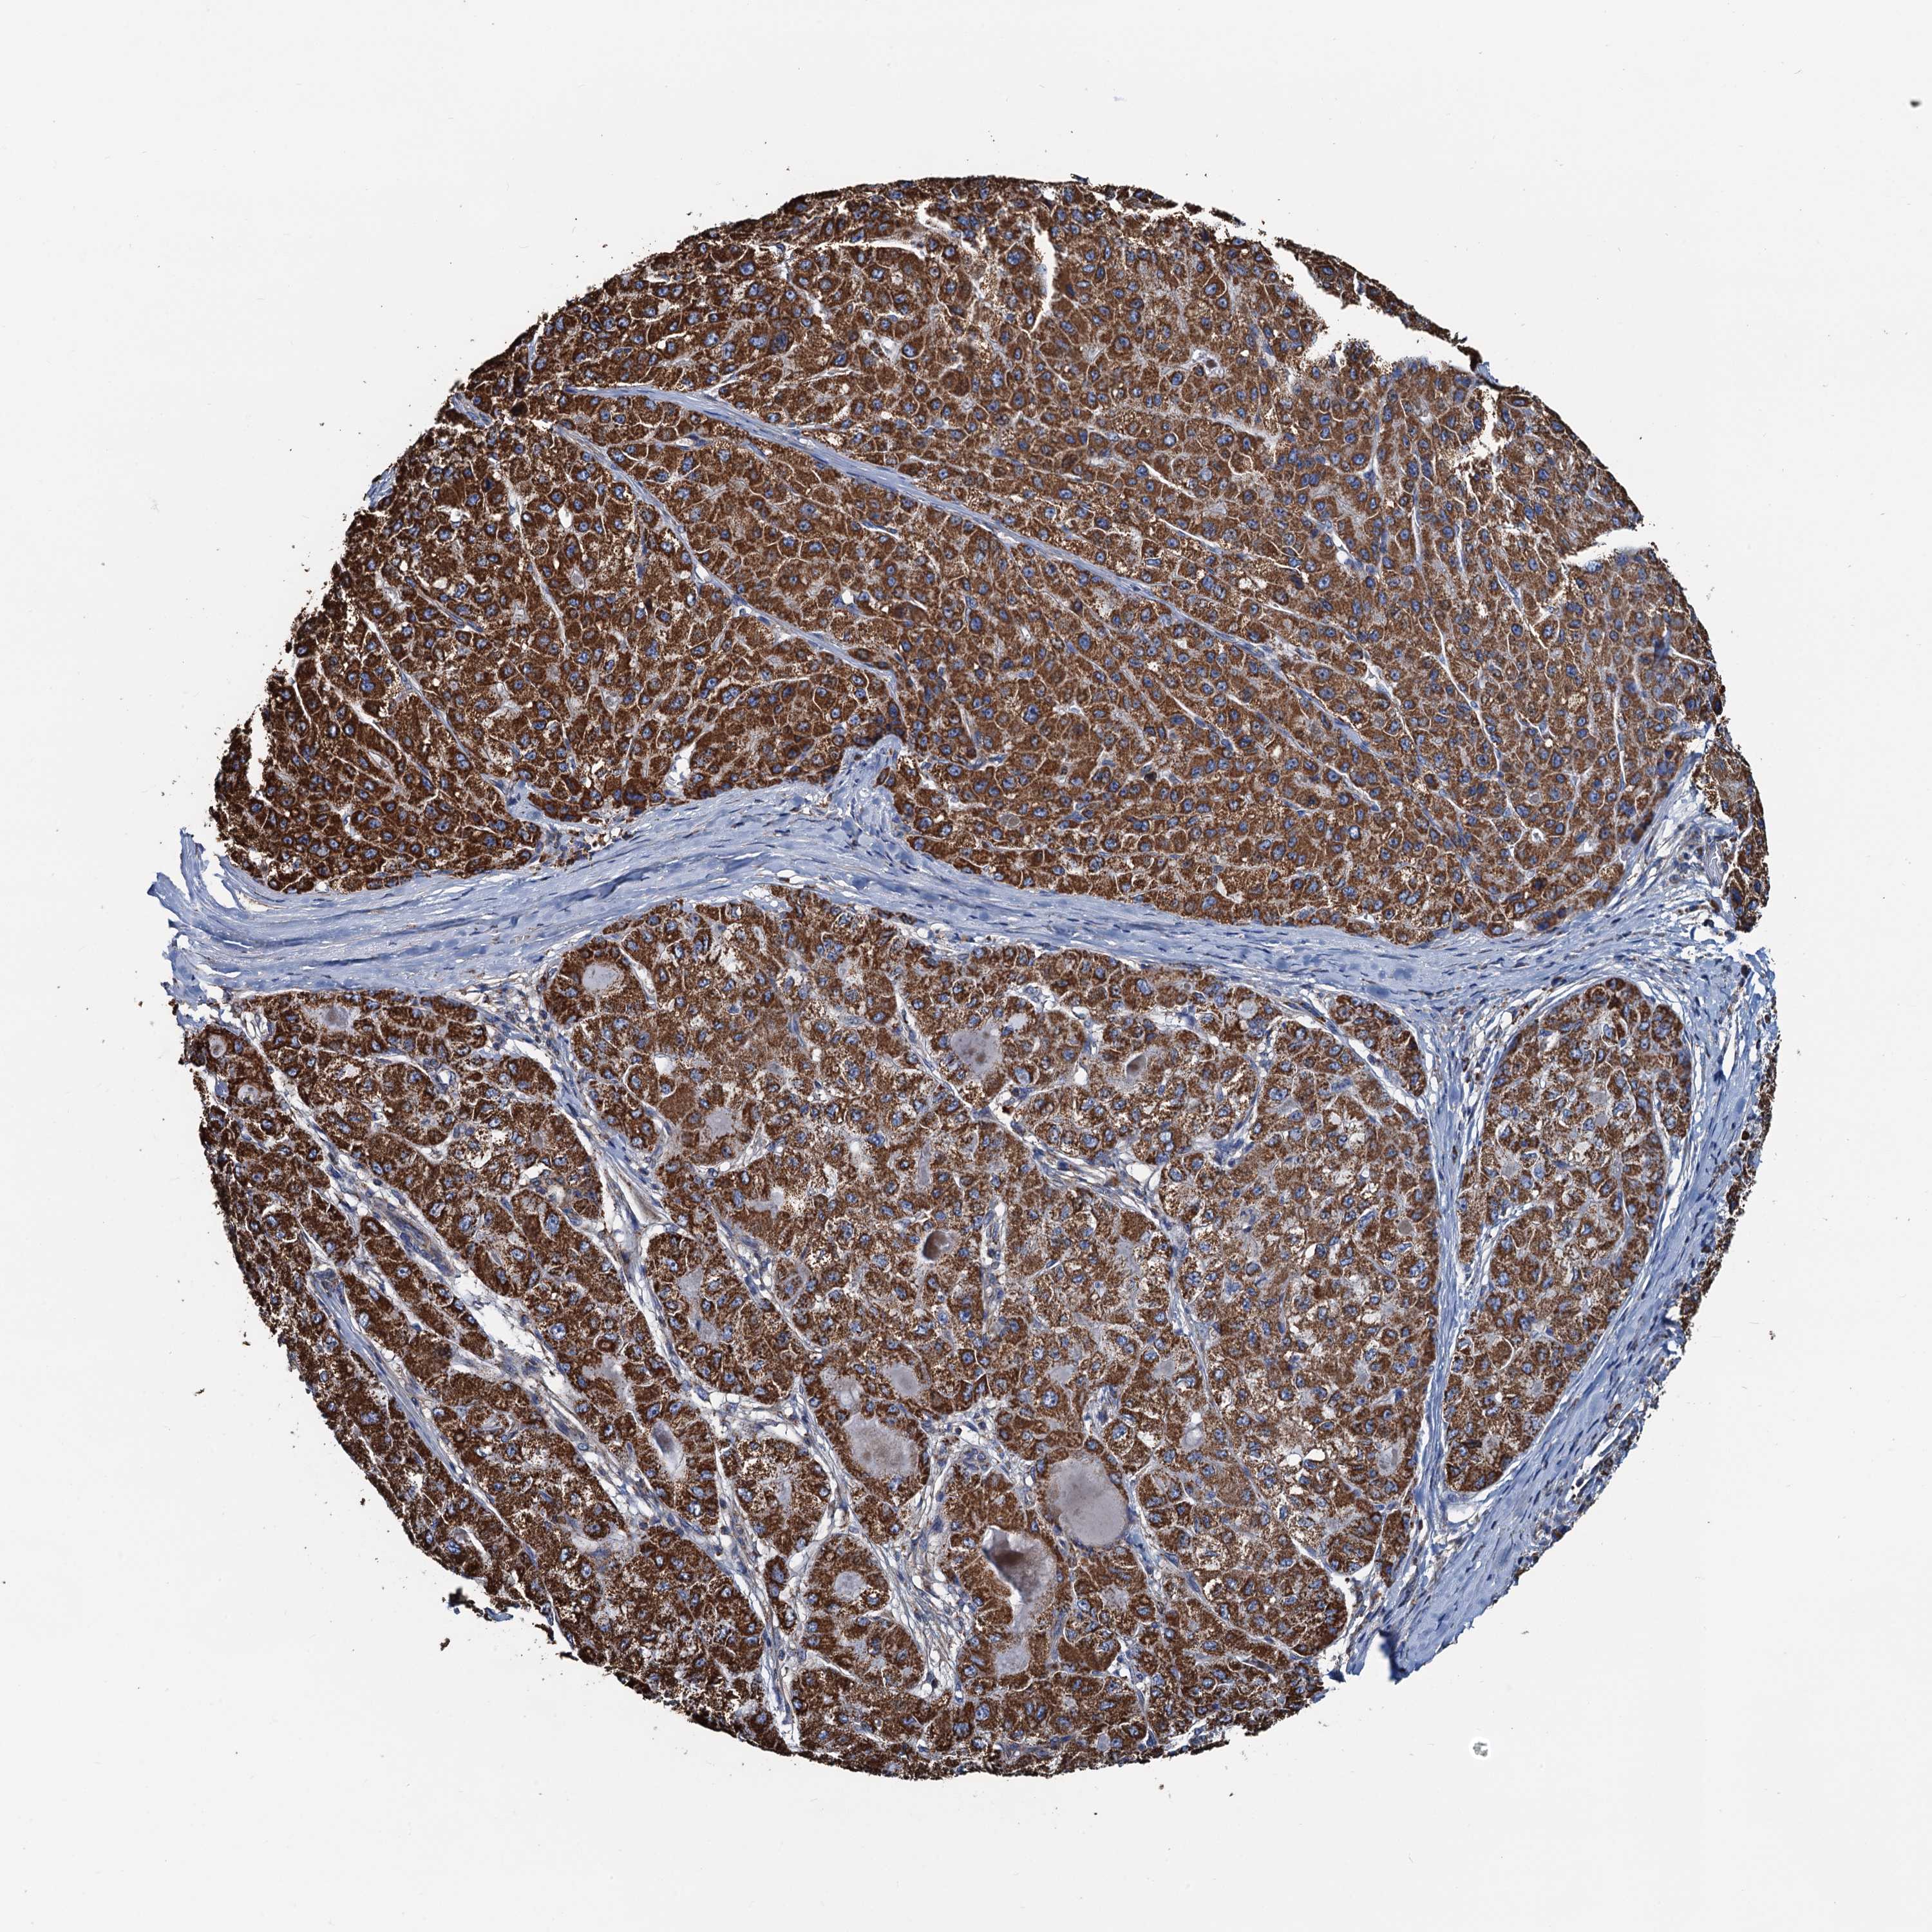

LIVER CANCER - Protein expressioni

A mouse-over function shows sample information and annotation data. Click on an image to view it in a full screen mode. Samples can be filtered based on level of antibody staining by selecting one or several of the following categories: high, medium, low and not detected. The assay and annotation is described here.

Note that samples used for immunohistochemistry by the Human Protein Atlas do not correspond to samples in the TCGA dataset.

Antibody stainingi

Antibody staining in the annotated cell types in the current human tissue is reported as not detected, low, medium, or high, based on conventional immunohistochemistry profiling in selected tissues. This score is based on the combination of the staining intensity and fraction of stained cells.

Each image is clickable and will lead to virtual microscopy that enables deeper exploration of all samples and also displays staining intensity scores, fraction scores and subcellular localization as well as patient and tissue information for each sample.

Antibody HPA039371

Antibody HPA040174

Staining

High

Medium

Low

Not detected

Intensity

Strong

Moderate

Weak

Negative

Quantity

>75%

75%-25%

<25%

None

Location

Nuclear

Cytoplasmic/membranous

Cytoplasmic/membranous,nuclear

Cholangiocarcinoma

Carcinoma, Hepatocellular, NOS